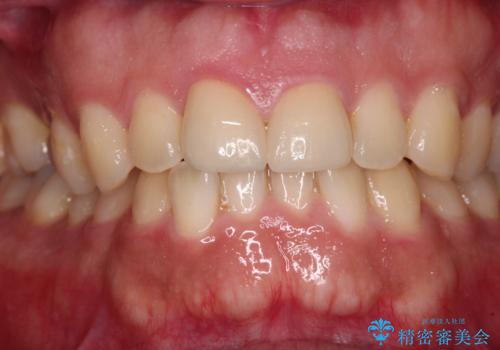

セラミックインレーを装着したことで、とても自然な仕上がりとなりました。

患者様も大きく口を開けても気にならなくなった、大変喜んでくださいました。